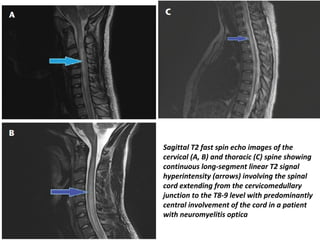

Sagittal T2 fast spin echo images of the

cervical (A, B) and thoracic (C) spine showing

continuous long-segment linear T2 signal

hyperintensity (arrows) involving the spinal

cord extending from the cervicomedullary

junction to the T8-9 level with predominantly

central involvement of the cord in a patient

with neuromyelitis optica

Sagittal T2 fastspin echo images of the cervical (A, B) and thoracic (C) spine showing continuous long-segment linear T2 signal hyperintensity (arrows) involving the spinal cord extending from the cervicomedullary junction to the T8-9 level with predominantly central involvement of the cord in a patient with neuromyelitis optica